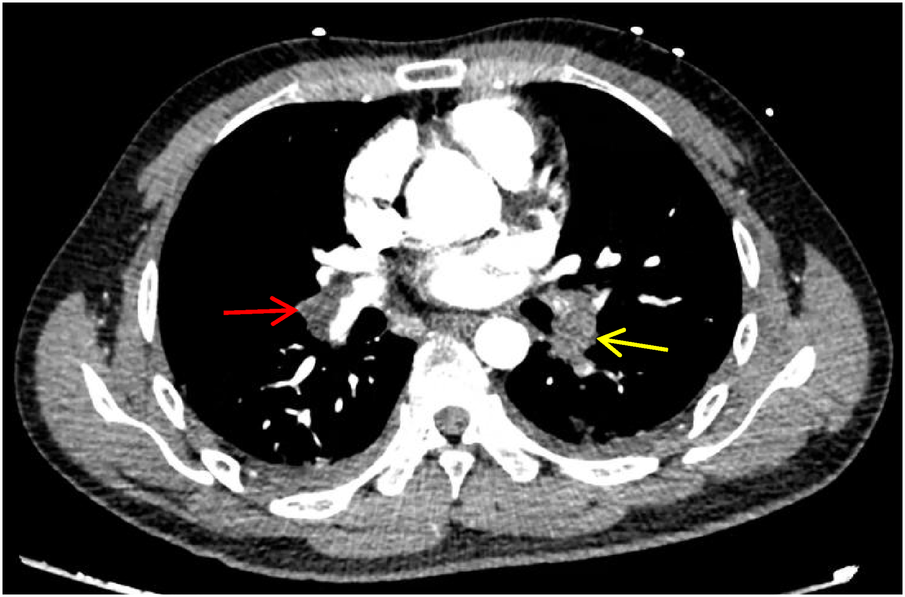

A 28-year-old male patient, previously in good health, was admitted to the hospital due to a cough and chest pains. In August 2023, the patient developed a cough without any obvious cause, with bloody sputum. On September 8, 2023, he was admitted to a local hospital with a cough and right-sided chest pain. Blood tests revealed elevated D-dimer (5.79 mg/L, ↑) and whole blood C-reactive protein (48.28 mg/L, ↑). CTPA confirmed acute pulmonary embolism with multiple filling defects in both pulmonary arteries (Figure 1). He was subsequently diagnosed with acute pulmonary embolism and pneumonia after receiving alteplase (100 mg), morphine (10 mg), and cefmetazole (2 g every 8 h). Due to severe chest pain, breathing difficulties, and hypoxemia (SPO2 around 85% at rest), the patient was referred to our intensive care unit (ICU) on September 14, 2023. The patient's father and grandfather have a family history of lower limb venous thrombosis. He is neither obese nor sedentary, and he has no history of smoking or alcohol consumption.

Figure 1

CTPA shows multiple pulmonary artery-filling defects in both lungs. The red arrow represents the main trunk of the right pulmonary artery, and the yellow arrow represents the lower left pulmonary artery.